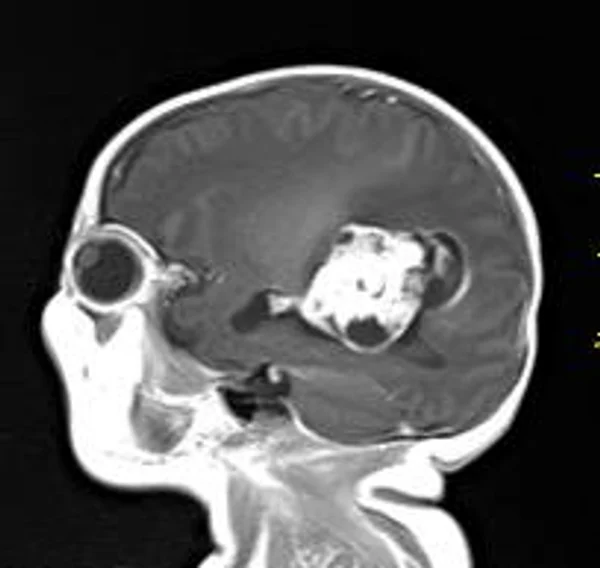

В качестве примера приведены 2 случая хирургического лечения новорожденных с врожденными опухолями головного мозга и позвоночного канала. У новорожденной девочки опухоль (хориодпапиллома) располагалась в области треугольника правого бокового желудочка (рис. 28 а, б). В возрасте 2-х недель жизни опухоль удалена. По данным МРТ головы с внутривенным введением контрастного препарата выполненной через 2 дня после операции опухоль удалена тотально (рис. 28 в). Послеоперационных осложнений не наблюдалось. У второго пациента 2-х нед. жизни врождённая опухоль (нейробластома) располагалась в позвоночном канале на уровне Th10-L3 позвонков (рис. 29 а) и распространялась в забрюшинное пространство. Клиническая картина заболевания складывалась из нижнего вялого парапареза и нарушения функции тазовых органов. Во время операции остистые отростки Th 11-L3 позвонков рассечены по средней линии. Дужки 6 данных позвонков надломлены и разведены в стороны. Опухоль располагалась экстрадурально, отделена от дорзальной поверхности дурального мешка и корешков спинно-мозговых нервов, после чего полностью удалена из позвоночного канала. Половинки дужек позвонков сведены к средней линии и сшиты между собой. Опухолевый узел в забрюшинном пространстве через 2 нед. удален онкологами. Через год после операции по данным МРТ рецидива опухоли нет (рис. 29 б). При спондилографии дефектов задней стенки и деформаций позвоночника не выявлено (рис. 29 в). Мальчик ходит, мочу и кал удерживает.